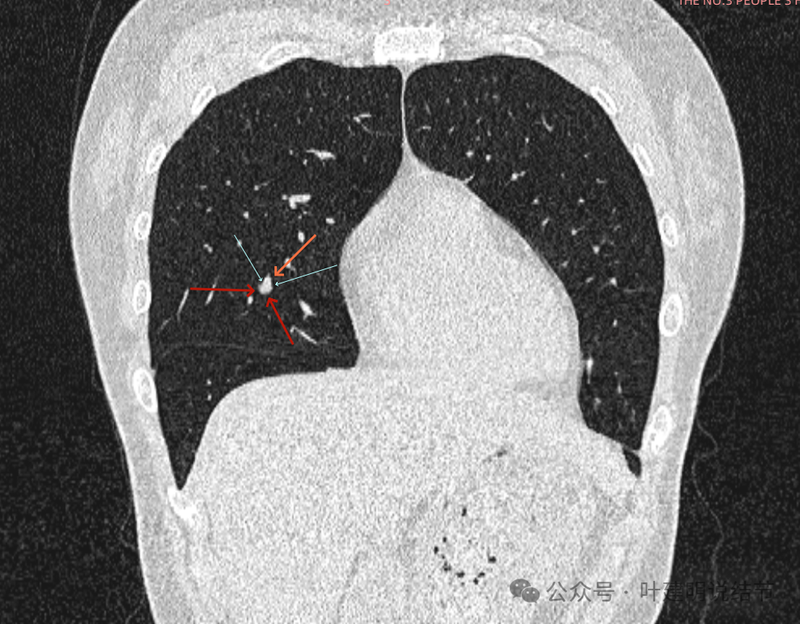

再看冠状位影像:

血管与病灶的关系,两者密度稍不同,天蓝色细箭头所指是分界线。

血管征明显。

血管围着病灶,病灶有膨胀性,表面欠平滑。

不而有膨胀性,血管贴着并被压迫。

边缘欠平滑,邻近血管间隙欠清晰。

血管贴着,结节膨胀。

也示血管与病灶的关系。

结节实性。

纵隔窗这个角度明显见到蓝色箭头所指的血管被病灶侵蚀,而且血管与病灶密度的不同。